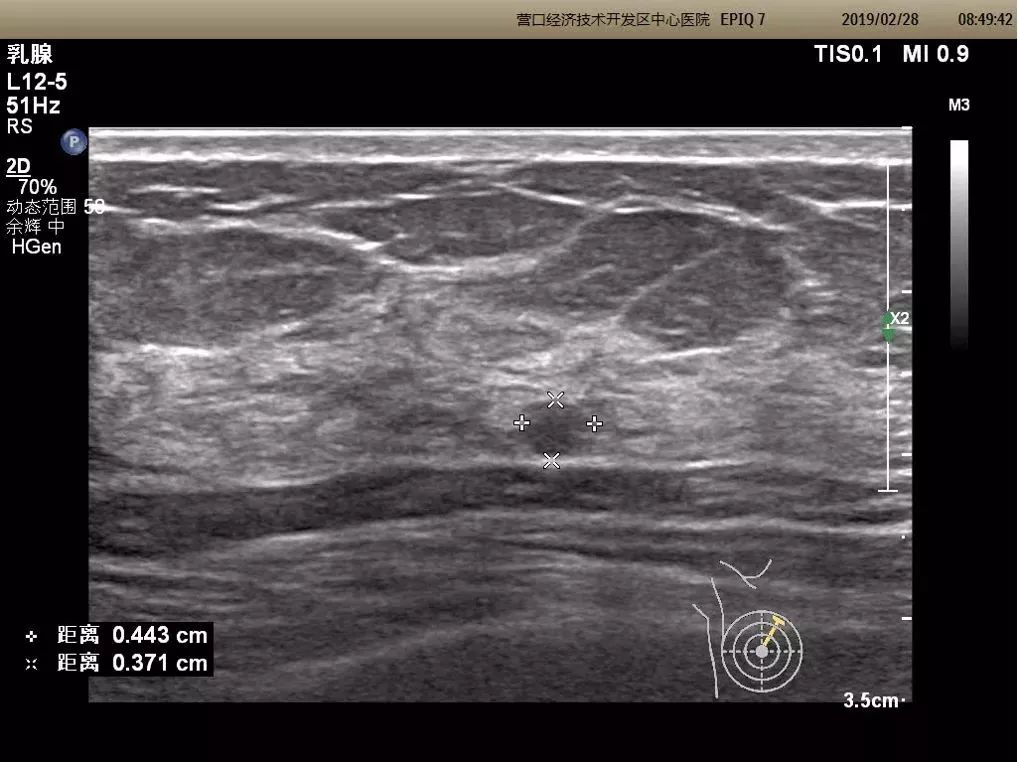

浅表器官三维超声成像

可显示甲状腺、乳腺结节的三维立体图像,可多角度、多切面观察病灶,对选定区域切割成像,能够清晰显示结节的空间位置、内部细微结构及内部血管树构型,同时进行连续性观察和定量和半定量测量。对肿块的良恶性鉴别提供较大帮助。